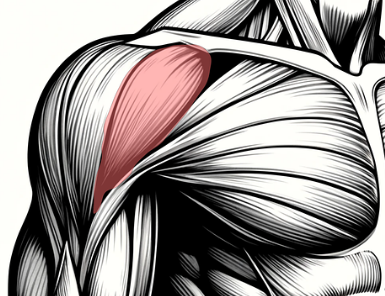

회전근개는 극상근, 극하근, 소원근, 견갑하근이라는 네 가지 근육으로 구성돼 있어요. 이 네 근육은 어깨 관절을 감싸고 있으며, 팔을 회전시키거나 들 때 매우 중요한 역할을 해요. 팔을 옆으로 들거나 위로 올리는 대부분의 움직임에 관여한다고 보면 돼요.

극상근은 어깨뼈 위쪽에 위치하고 있으며 팔을 옆으로 들어올릴 때 처음 시작을 담당해요. 극하근과 소원근은 팔을 바깥으로 회전시키는 역할을 해요. 견갑하근은 팔을 안쪽으로 돌리는 데 중요한 근육이랍니다. 각각의 역할이 다르지만, 네 근육이 함께 움직이면서 어깨의 복잡한 운동을 가능하게 해줘요.

이 근육들은 힘줄로 이어져 있어 어깨뼈에 단단히 부착돼 있고, 팔을 올리거나 돌릴 때마다 빠르게 수축과 이완을 반복해요. 그래서 회전근개에 문제가 생기면 단순한 통증이 아니라, 팔의 전반적인 움직임 자체가 제한될 수 있어요.

회전근개는 어깨 관절의 안정성을 유지하는 데도 중요한 역할을 해요. 어깨는 신체에서 가장 많이 움직이는 관절인 만큼 구조적으로 불안정한데, 회전근개가 그 불안정을 보완해 주는 거예요.